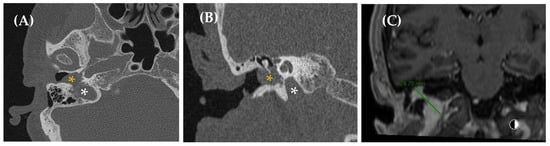

Figure 4. Dural arteriovenous fistula (dAVF) in a 65-year-old woman with a somatosound in the left ear, present for five years. The PT neither disappeared nor changed upon compression of the cervical vascular axis. MR angiography axial plane (image (A)) revealed findings suggestive of a dAVF (yellow arrow). Diagnostic–therapeutic arteriography (images (B), cone bean angio CT MPR in sagittal plane and (C), posteroanterior DSA view with injection of extracellular contrast agents) confirmed the presence of an AVF with arterial supply from the left occipital branch and superficial venous drainage to the left suboccipital region. Based on this finding, the fistula was embolized (yellow arrow, image (C)).

Imaging studies are required for dAVF diagnosis (Figure 4 and Figure 5). MRA may accurately detect the side and presence of fistulas, making it an appropriate screening and follow-up tool [54,55]. CTA is also considered an effective diagnostic technique, with Table 6 outlining the main signs that may indicate the presence of a dAVF on this test [47,56]. In fact, some studies have suggested that 4D dynamic CTA (CTA-4D) can achieve diagnostic concordance with DSA close to 100% [57,58,59,60]. Therefore, MRA and CTA are the diagnostic tools of choice, with a high detection rate for medium- and high-flow fistulas [22]. Low-flow fistulas can often be diagnosed using the minimally invasive DSA technique, which remains the gold standard for evaluating dAVF due to its excellent spatial and temporal resolution and its ability to delineate all aspects of the complex hemodynamic features of this condition. DSA also assists in planning endovascular or surgical treatment [10,47]. Thus, our recommendation is to use MRA as a screening method for dAVF, with definitive diagnosis established via DSA, a procedure performed only to assess neurological prognosis or when therapeutic intervention, such as embolization, is anticipated [22,50].